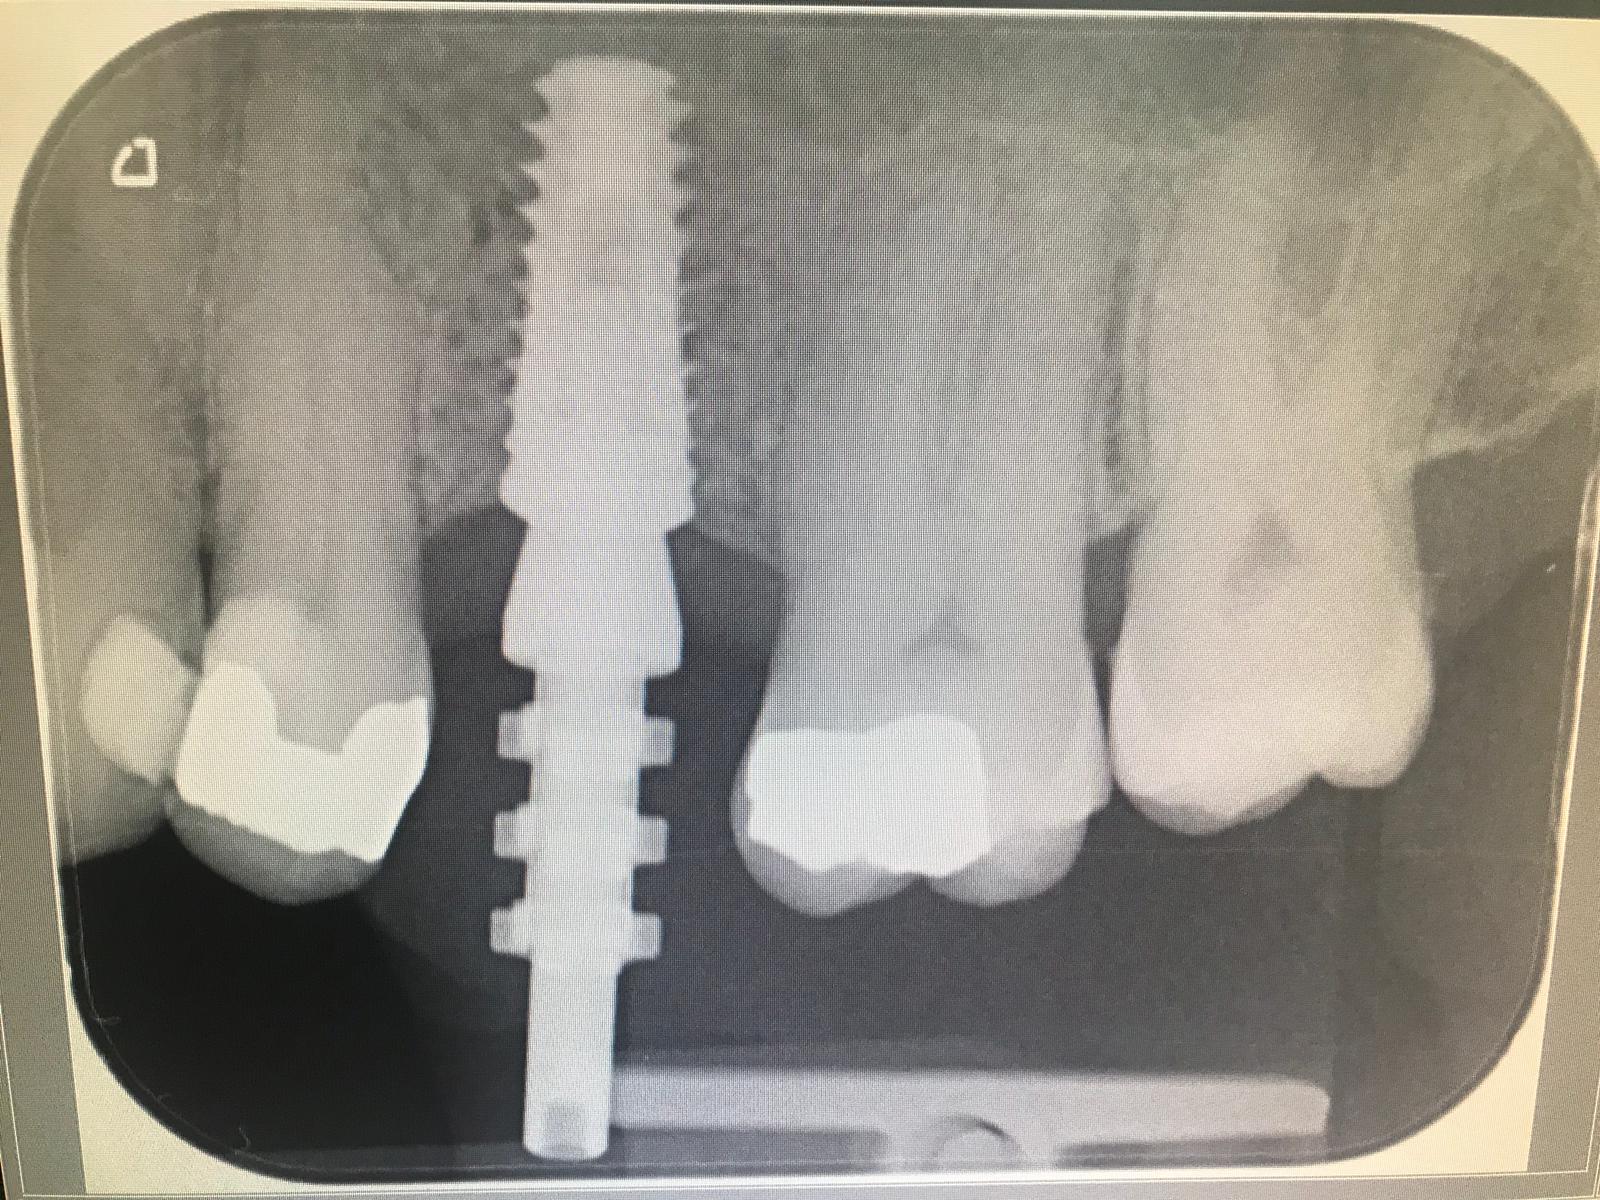

Dr Khattak has experience of over 15 years in dental implant solutions and we can arrange a free implant consult after your dental checkup. Dental implants can easily replace missing teeth and also help in better retention of dentures. We also provide full arch dental implants to replace lost teeth with implant supported bridges which are often referred to as ‘teeth in a day’ , All on four, AO4 or ‘teeth express’.